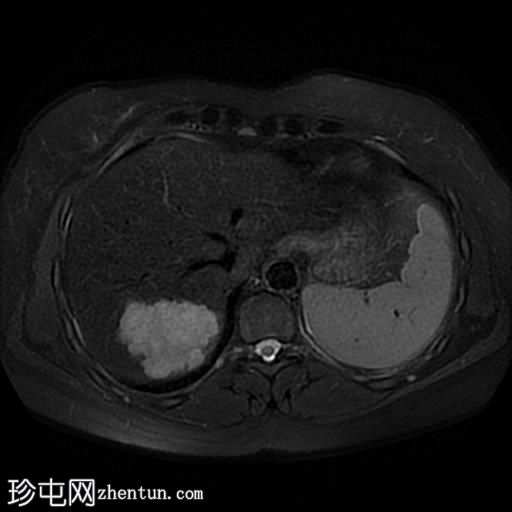

轴位

T2加权像

肝脏第7段可见一边界清晰的分叶状肿块。T1加权像呈低信号,T2/T2脂肪抑制序列呈高信号,动脉期呈不连续结节状周边强化,门静脉期呈向心性强化,延迟期完全强化。DWI序列呈高信号,ADC值呈混合信号。